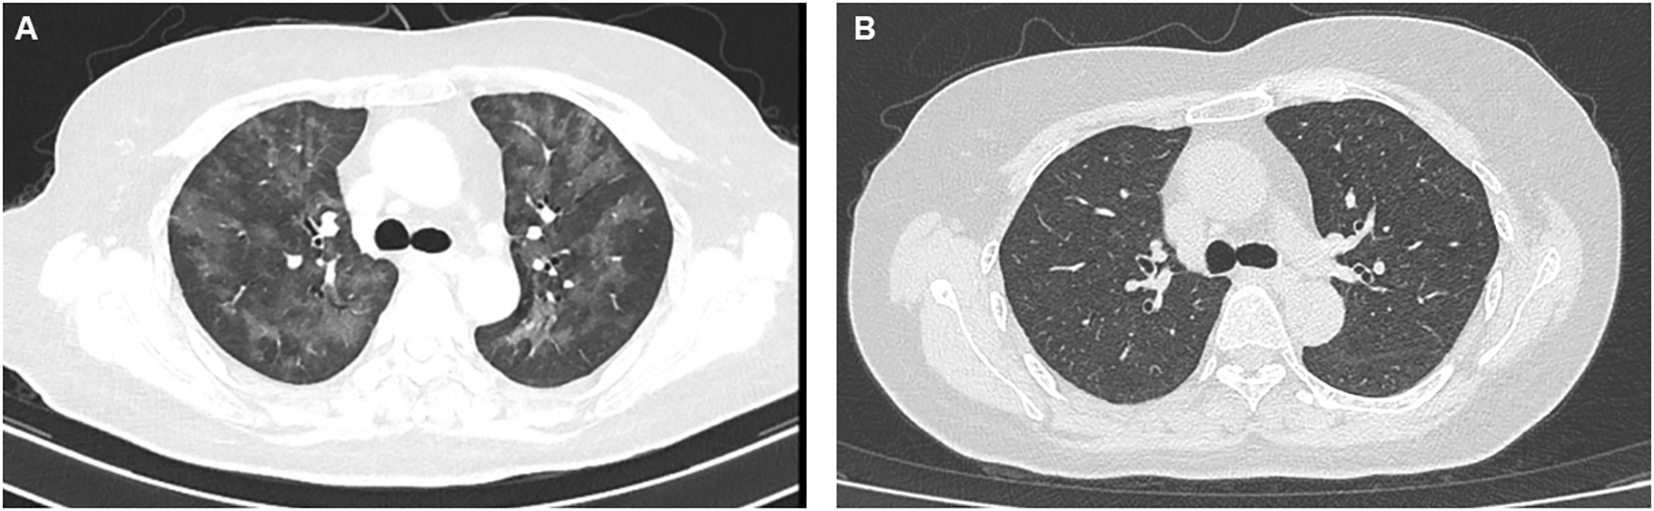

However, on June 30, 2021, the patient began complaining of shortness of breath after mild activity and abnormally elevated blood troponin up to 250 ng/L, along with the abnormal elevation of creatine kinase (up to 432 U/L) and lactate dehydrogenase (up to 325 U/L). No significant abnormalities were seen on the electrocardiogram, and she was diagnosed with grade 2 ICI-associated myocarditis. ICI therapy was immediately suspended and symptomatic treatment with methylprednisolone was administered. On September 2, 2020, the patient complained of increased chest tightness and shortness of breath, and blood troponin showed 47.3 ng/L. Chest CT reported interstitial pneumonia in both lungs (Figure 1A), and genetic testing of pathogenic microorganisms from alveolar lavage fluid was diagnosed as secondary Pneumocystis jirovecii infection due to immune depression. Targeted anti-infective therapy was given, along with symptomatic treatment with methylprednisolone combined with human immunoglobulin. Until November 2, 2021, the patient’s shortness of breath gradually improved, and the chest CT showed that the inflammatory manifestations of the lungs basically disappeared (Figure 1B), and the myocardial enzyme index returned to the normal range. However, unfortunately, due to the interruption of antitumor treatment for 5 months, the para-aortic lymph nodes were significantly enlarged and fuses into clusters, which was considered as tumor progression.

Figure 1

The performance of CT scan of the pulmonary infection induced by hormone use (A) and the result of CT image after anti-infection as well as symptomatic treatment (B).